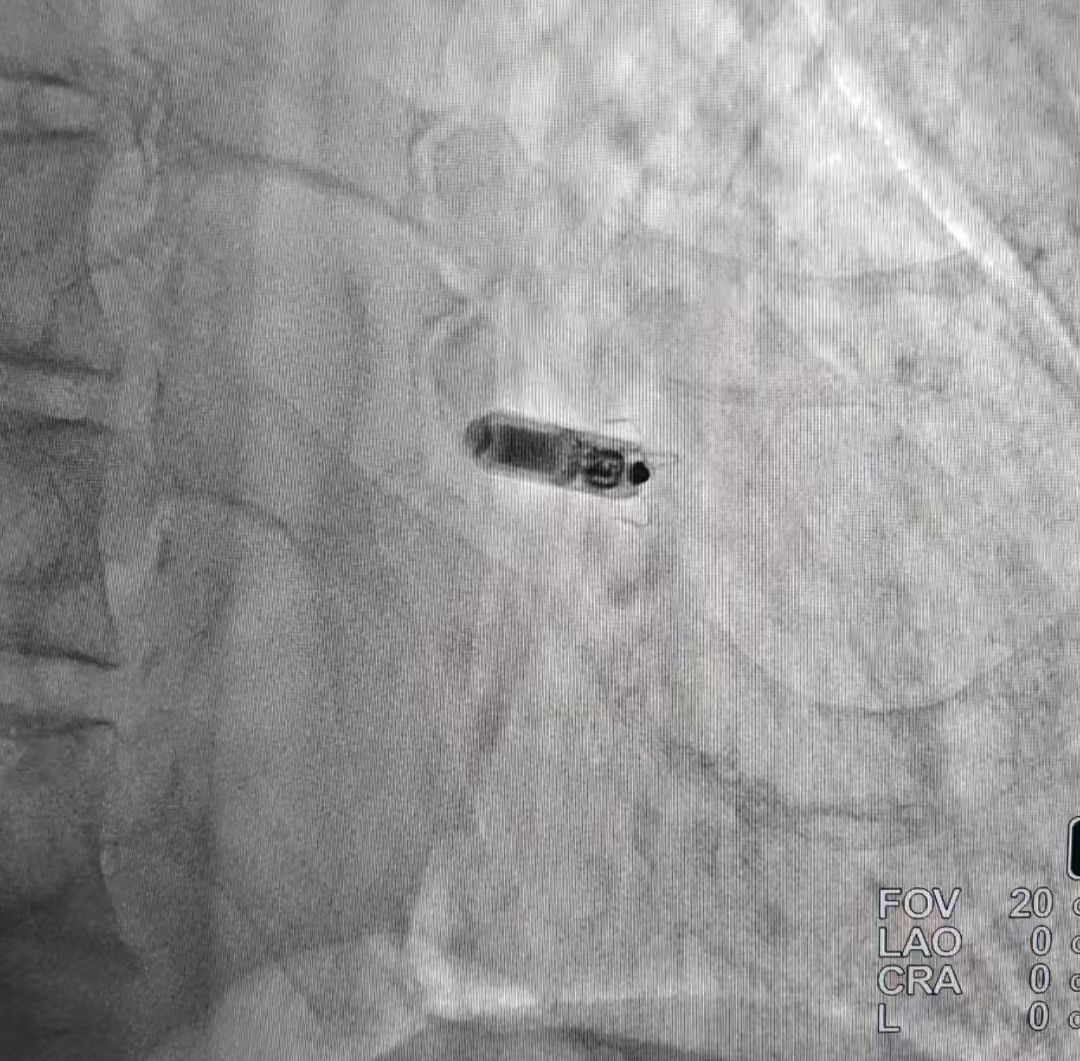

第一位患者是一名70岁男性患者,因反复因心衰加重住院,患者有冠心病、高血压、房颤、慢阻肺既往病史。医生行检查后发现,患者左室射血分数仅0.39,动态心电图示患者持续性房颤伴三度房室传导阻滞、长RR间歇,频发室性早搏、短阵室速,具有起搏器植入指征。考虑到患者高龄、体型消瘦、房颤病史,传统单腔起搏器存在囊袋感染、伤口愈合迟缓等并发症风险,且需长期口服利伐沙班抗凝治疗,增加切口出血及感染风险,慢阻肺病史,此次入院合并肺部感染,三尖瓣关闭不全伴中量反流,肺动脉高压,全身状况较差无法耐受较长时间手术。医生经讨论决定采用新型无导线起搏器(Micra)救治患者。术中医生穿刺右侧股静脉,经鞘管输送Micra无导线起搏器顺利至右室中位间隔区域,测试心室起搏阈值0.5V,阻抗920Ω,感知8.6mV,参数良好满意。术后第二天患者活动后乏力气短等症状明显改善。